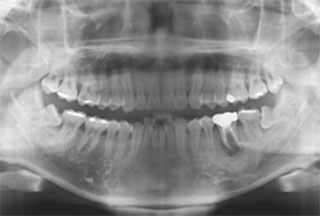

¹ßÄ¡ Áï½Ã ÀÓÇöõÆ® ÀüÈÄ»çÁø

- 1

½Ã¼ú Àü ¹æ»ç¼±»çÁø - 2